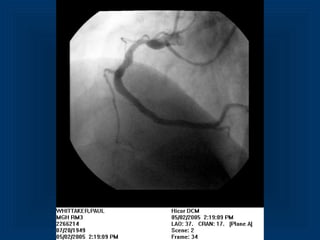

Occlusion 1st

diagonal

branch

Multiplanar Reconstruction